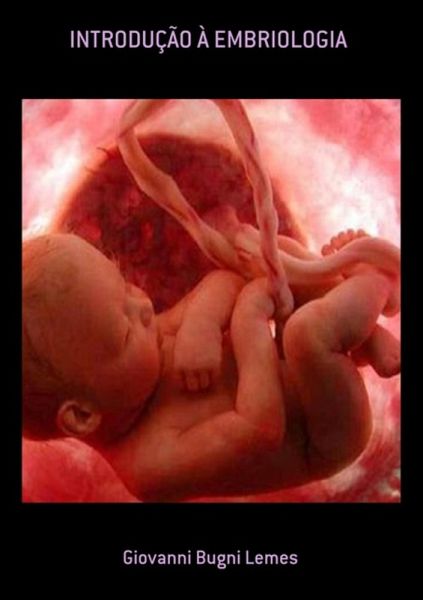

Introdução À Embriologia (eBook, PDF)

Este livro demonstra de forma didática todo o conceito da embriologia. A Embriologia é o ramo da biologia e da medicina que estuda o desenvolvimento do ser vivo desde a fecundação do ovo até o final do estado embrionário.